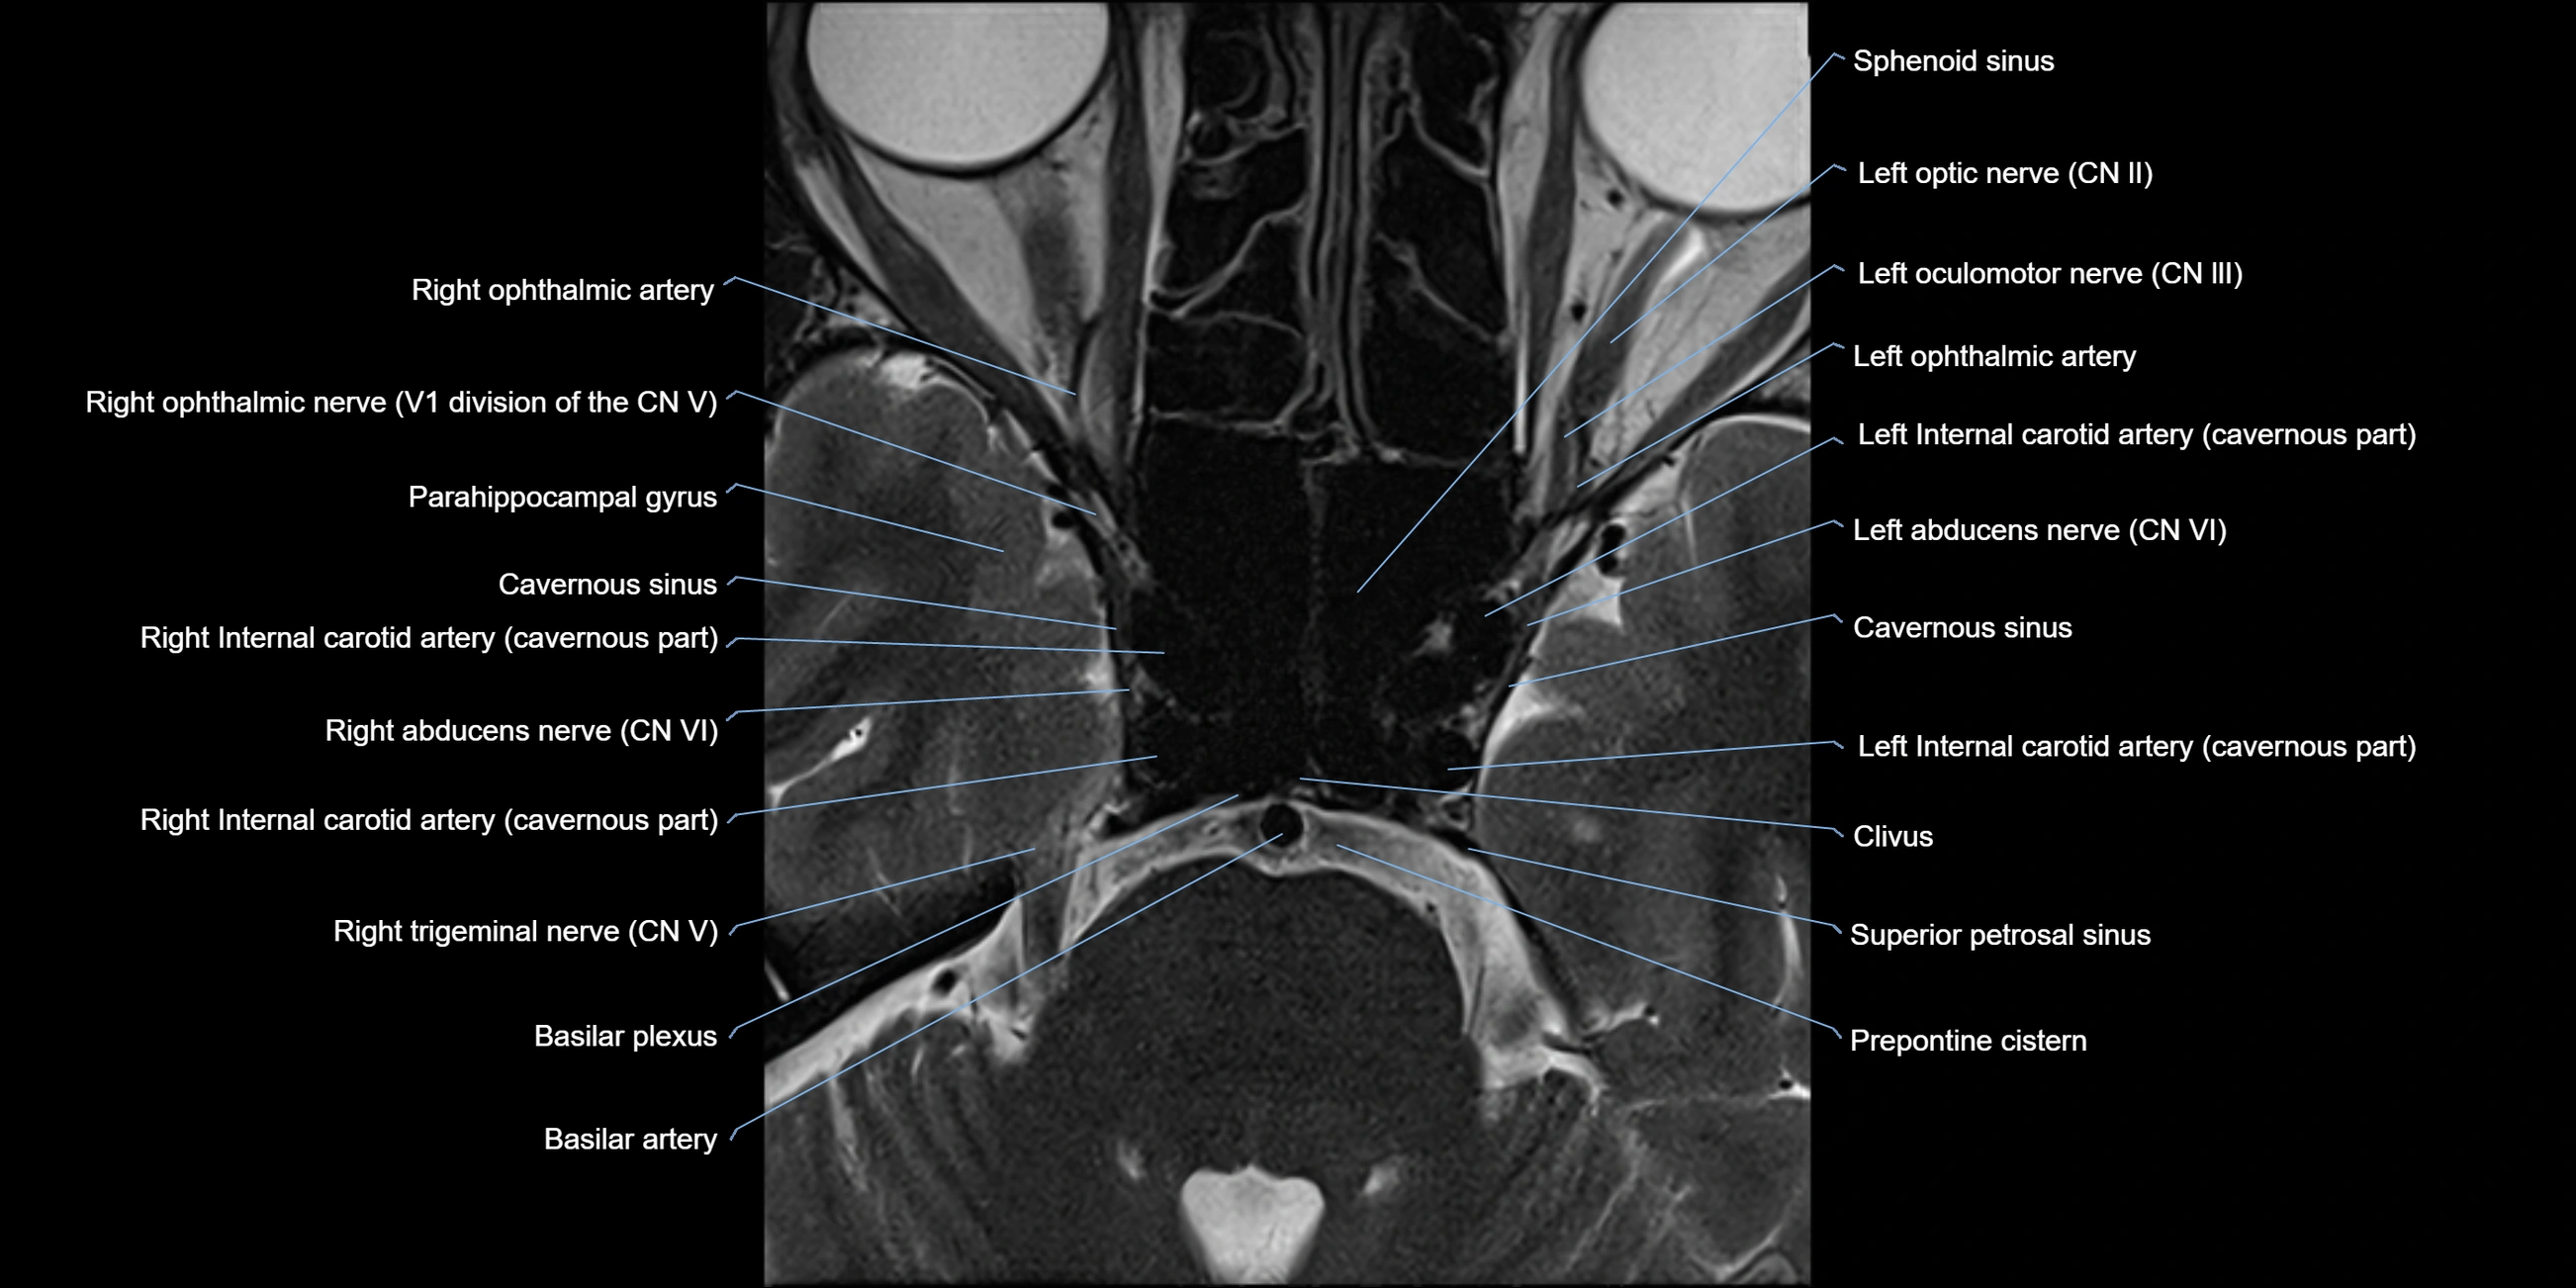

MRI Appearance

-

The abducens nerve is a small, thin, linear structure

Best visualized on high-resolution T2-weighted 3D MRI sequences (e.g., FIESTA or CISS)

Seen as a hypointense (dark) line running from the brainstem at the pontomedullary junction, traversing the prepontine cistern, and entering Dorello’s canal under the petrosphenoidal ligament, then into the cavernous sinus, and finally the orbit

May be challenging to visualize in standard MRI due to its small size

Pathology may be inferred by absence, displacement, or enhancement of the nerve

MRI images